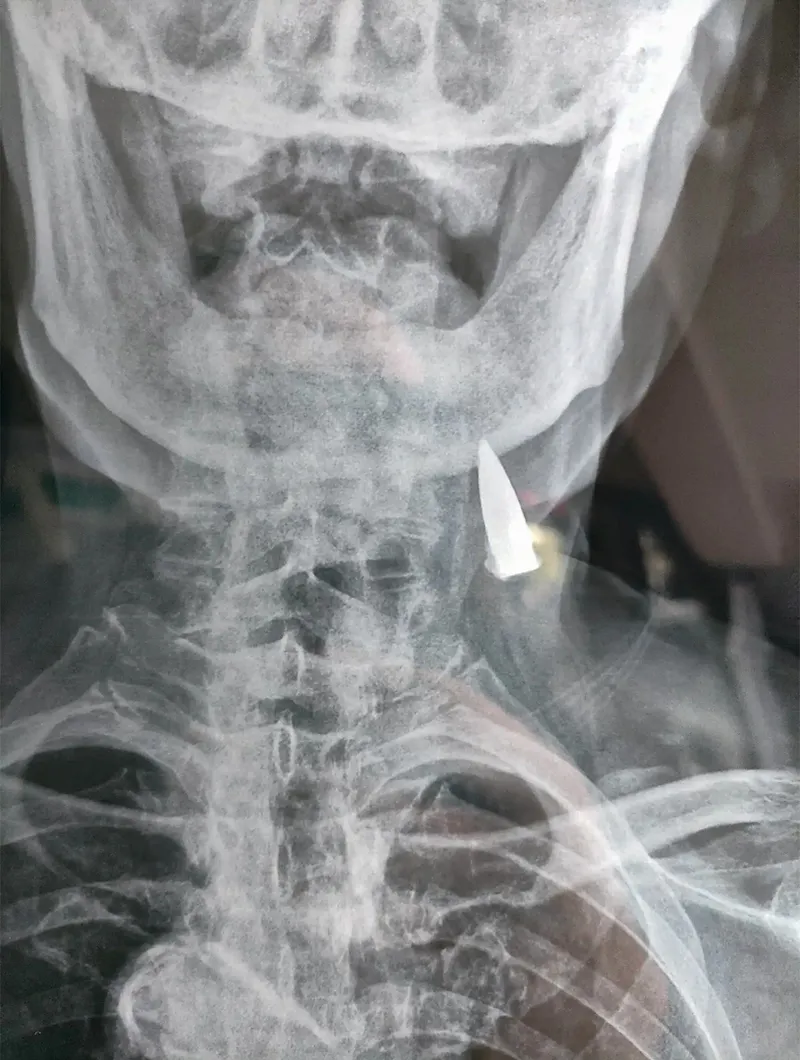

FOTO Un veteran a trăit 77 de ani cu un glonț în gât. În 1945 a fost împușcat și nu a știut până azi

Medicii care au efectuat o radiografie au fost uimiți să descopere un glonț înfipt în gâtul unui veteran al armatei la aproape 80 de ani după ce acesta a suferit rana - și nici măcar nu și-a dat seama că se afla acolo.

Radiografia unui fost soldat a dezvăluit o surpriză șocantă, când s-a dovedit că un glonț se afla încă în gâtul său după 80 de ani.

Zhao He, în vârstă de 95 de ani, avea glonțul înfipt în corp încă din timpul celui de-al Doilea Război Mondial, dar nici măcar nu a știut că se afla acolo până când personalul medical de la un spital din Shandong, China, a descoperit obiectul vechi de zeci de ani.

În mod miraculos, experții medicali spun că glonțul nu i-a provocat nicio problemă lui Zhao - în ciuda faptului că a rămas înfipt în gât timp de 77 de ani.

Din această cauză și din cauza vârstei lui Zhao, glonțul nu va fi îndepărtat, deoarece scoaterea lui ar implica o operație riscantă.